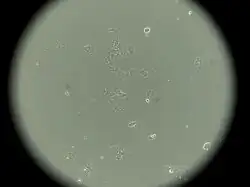

MCF-7 is a breast cancer cell line isolated in 1970 from a 69-year-old White woman.[1] MCF-7 is the acronym of Michigan Cancer Foundation-7, referring to the institute in Detroit where the cell line was established in 1973 by Herbert Soule and co-workers.[2] The Michigan Cancer Foundation is now known as the Barbara Ann Karmanos Cancer Institute.[3]

Prior to MCF-7, it was not possible for cancer researchers to obtain a mammary cell line that was capable of living longer than a few months.[4]

MCF-7 cells have the following characteristics:[2][5][6][7][8][9]

- Primary tumor (invasive breast ductal carcinoma)

- Originate from pleural effusion

- Luminal epithelial phenotype

This cell line retained several characteristics of differentiated mammary epithelium, including the ability to process estradiol via cytoplasmic estrogen receptors and the capability of forming domes.